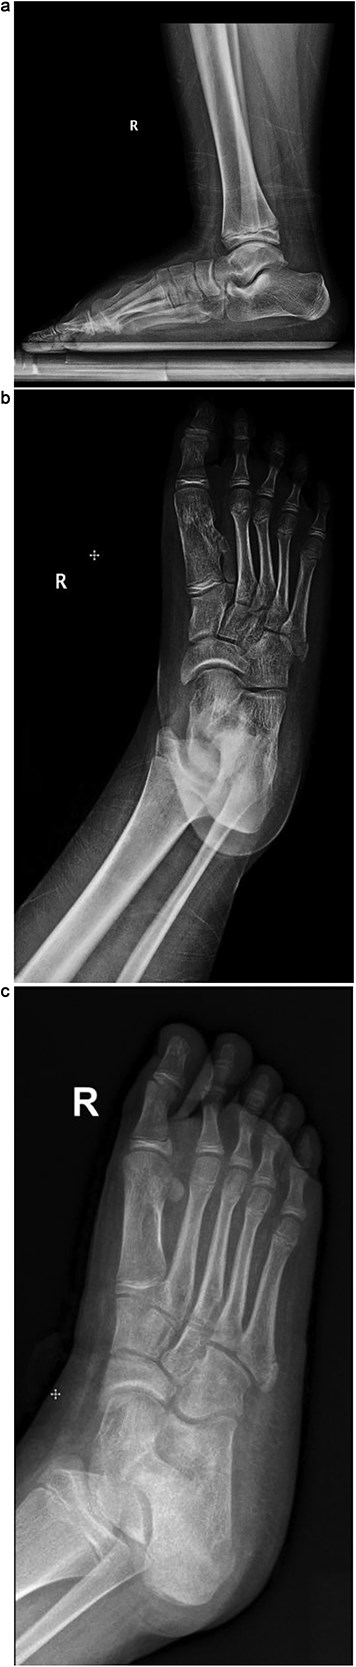

Plain radiographs revealed a bony mass extending from the medial cuneiform to the first metatarsal, with the first and second intermetatarsal space widening (Fig. 1). Magnetic resonance imaging (MRI) was performed to better characterize the mass (Fig. 2). Musculoskeletal radiologists reported the presence of an abnormal rudimentary bone that was interposed between the first and second metatarsal bones, with pseudo-articulation and ankylosis with the lateral aspect of the mid-metatarsal shaft of the hallux, causing widening and deformity, suggesting a supernumerary rudimentary metatarsal bone. An osteochondroma was also considered in the differential diagnosis, but the cartilage cap was not clearly visible. As daily activities were significantly affected, the patient’s guardian preferred surgical excision over more conservative measures, which had previously been unsuccessful.

Coronal T1-weighted MRI of the right foot showing a rudimentary bone interposed between the first and second metatarsals with pseudo-articulation and ankylosis with the midshaft of the first metatarsal.